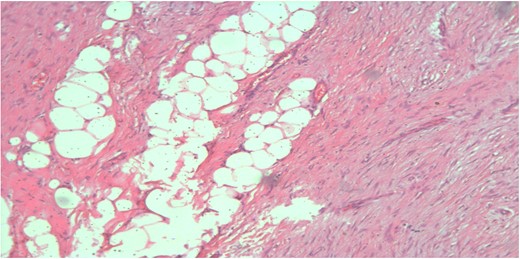

A 26-year-old female presented to our unit with recurrent right breast lump that was excised 6 years before with no available documented data. Physical examination revealed hard painless swelling occupying the medial quadrant of the right breast below the site of the old incision with no clinically palpable axillary LNs. Ultrasonography reported an ill-defined heterogeneous hypoechoic soft tissue lesion. Core needle biopsy revealed dense collagen bundles. Excision of the mass was done and paraffin sections stained by Hematoxylin and Eosin (H&E) showed benign tumoral proliferation formed of spindle cells arranged in small clustered fasicles separated by thick collagen bands (Fig. 1). Further IHE studies confirmed the diagnosis of fibromatosis supported by positive nuclear staining for B-catenin (Fig. 2). And 18 months later, she came with abdominal wall swelling, underwent CT scanning and found to be multiple soft tissue masses at the lower anterior abdominal muscles at the right lumbar and iliac regions.The largest measured ~13 × 10 cm. Core needle biopsy revealed spindle cell proliferation consistent with fibromatosis confirmed by positive reaction for SMA (Fig. 3) and B-catenin. Lesions were excised with free margins and reconstruction of the abdominal wall was carried out using a double face mesh. Final pathology report was consistent with fibromatosis confirmed by positive reaction for SMA and B-catenin.The patient had smooth postoperative course.

Spindle cell proliferation formed of bland looking cell arranged in short fascicles with dissection of breast fat lobules at the periphery (H&E, ×100x).